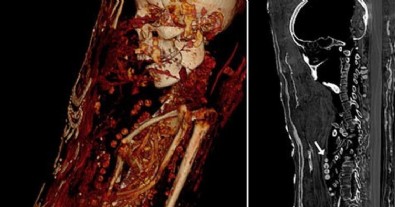

Mısır’da 400 yıl önce gömülen mumyaların gizemi bilgisayarlı tomografi sonucu ortaya çıktı. Mısır’da 1615 yılında gömülen üç mumyanın detayları bilgisayarlı tomografi sayesinde ortaya çıktı.Yirmili yaşlarda bir erkek, otuzlu yaşlarda bir kadın ve 17-19 yaşları arasında bir genç kıza ait olan mumyaların, alçı kaplı tabutların içerisinde muhafaza ediliyor.

Bilim adamlarının bilgisayarlı tomografi ile incelediği mumyaların tüm organlarıyla birlikte mücevher ve altın sikkelerle gömüldükleri ortaya çıktı. Araştırmacılar, incelemelere göre, söz konusu üç kişinin de sağlık problemleri nedeniyle erken yaşta öldüklerini belirtti.